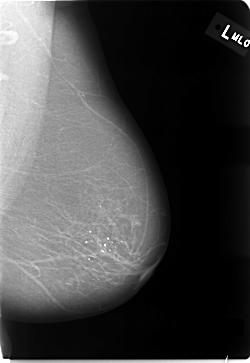

C_0011_1.LEFT_MLO

LEFT_MLO LINES 5800 PIXELS_PER_LINE 4000 BITS_PER_PIXEL 12 RESOLUTION 50 NON_OVERLAY